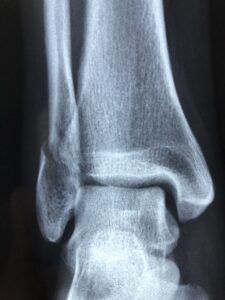

골수염은 뼈 속에 있는 조직에 세균이 침투해 염증이 생기는 상태를 말합니다. 뼈는 겉으로 단단해 보이지만 내부에는 혈관과 신경, 골수가 있어 외부에서 들어온 균이 퍼질 수 있는 구조를 가지고 있습니다.

염증이 생기면 뼈 주변 조직까지 영향을 받아 통증이나 부종, 열감이 나타날 수 있고, 진행되면 뼈 조직 일부가 손상되거나 괴사로 이어질 수 있습니다. 또한 감염이 오래 지속되면 회복이 늦어지고 만성적인 형태로 이어지기도 합니다. 골수염은 근육통이나 관절 통증과 구분이 어려운 경우도 있어 초기에는 알아차리기 쉽지 않습니다.

골수염은 주로 세균에 의해 발생하며, 가장 흔한 원인은 포도상구균입니다. 세균은 혈액을 통해 뼈로 전파되거나 외상, 수술, 피부 감염 등으로 뼈에 직접 침투할 수 있습니다.

또한, 만성 질환(당뇨병, 면역력 저하 등)이나 혈액순환 장애가 있는 경우 감염의 위험이 높아집니다. 골절이나 관절 치환 수술 후 감염이 발생할 수 있으며, 드물게 결핵균이나 기타 바이러스가 원인이 될 수도 있습니다. 골수염은 감염이 뼈에 깊이 침투하여 염증을 일으키므로, 초기 대응이 중요합니다.